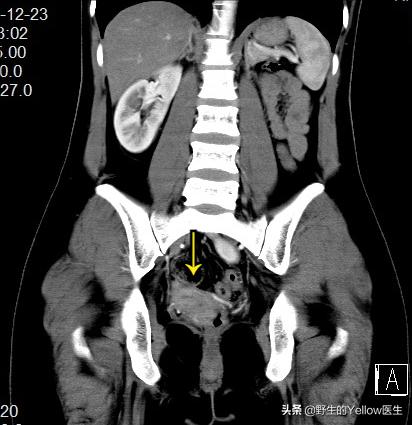

同时,子宫也有发育畸形。正常人子宫有两个宫角,通向同侧的输卵管,而她只有一个宫角——单角子宫。

这个病人恰好子宫跟肾脏在分化的过程中发生了点小问题,导致了右侧单角子宫跟左侧异位肾。然后左侧的卵巢没有子宫帮忙固定,就在盆腔游离。结果她左侧腹股沟管比较薄弱,卵巢就掉进左侧腹股沟管,形成左侧腹股沟卵巢疝。